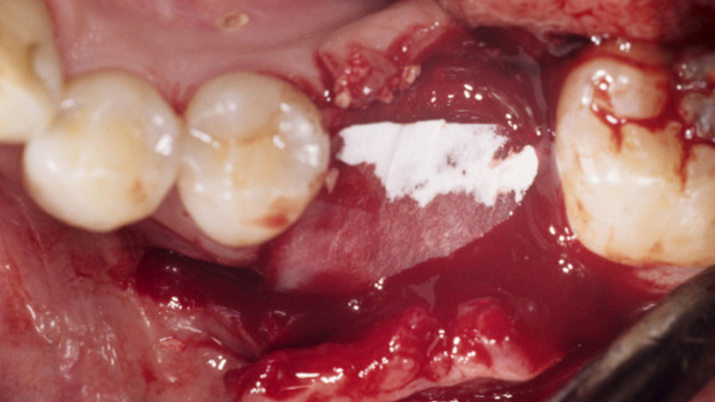

Clinical case: Single molar implant with bone augmentation

- Courtesy of Dr. Jung Sam Lee, Korea -

Keywords

AnyOne, bone augmentation, osteotomy socket, peri-implant tissue, autogenous bone, GBR, single replacement, Auto-Max, Dr. Jung Sam Lee

Products:

AnyOne implant system, Auto-Max